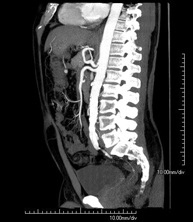

- Angio-TC aorta abdominal

Prueba diagnóstica no invasiva que consiste en el estudio de la arteria aorta abdominal obteniendo imágenes de alta definición anatómica mediante el empleo de un equipo de TC (Tomografía Computarizada) y de contraste yodado. La calidad de las imágenes permite realizar reconstrucciones en 2D y 3D gracias a estaciones de trabajo especializadas en el estudio arterial. Está indicado en aquellos pacientes con enfermedad vascular (aterosclerosis), en aneurismas de aorta, en pacientes con dolor abdominal de posible origen vascular, en estudios pre-quirúrgicos de lesiones adyacentes a la aorta abdominal como "mapa" vascular, etc. La información obtenida de forma no invasiva es indispensable para los pacientes que requieren tratamiento percutáneo o quirúrgico. En aquellos pacientes que solo requieren un seguimiento de las lesiones vasculares, esta técnica es la técnica no invasiva de elección junto con la angio-RM.

Prueba diagnóstica no invasiva que consiste en el estudio de la arteria aorta abdominal obteniendo imágenes de alta definición anatómica mediante el empleo de un equipo de TC (Tomografía Computarizada) y de contraste yodado. La calidad de las imágenes permite realizar reconstrucciones en 2D y 3D gracias a estaciones de trabajo especializadas en el estudio arterial. Está indicado en aquellos pacientes con enfermedad vascular (aterosclerosis), en aneurismas de aorta, en pacientes con dolor abdominal de posible origen vascular, en estudios pre-quirúrgicos de lesiones adyacentes a la aorta abdominal como el "mapa" vascular, etc. La información obtenida de forma no invasiva es indispensable para los pacientes que requieren tratamiento percutáneo o quirúrgico. En aquellos pacientes que solo requieren seguimiento de las lesiones vasculares, esta técnica es la técnica no invasiva de elección junto con la angio-RM.